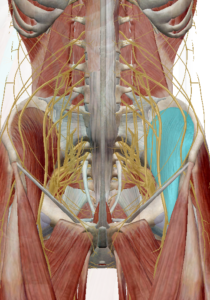

(4) 이상근

이상근은 천골의 앞쪽에서 부터 대퇴골의 위쪽을 향하고 있습니다.

고관절을 외회전 시키며 이상근 아래로 좌골신경이 지나가면서 좌골신경통의 원인으로 주목받고 있습니다.

이상근이 주목받는 또 다른 이유로는 기능의 변화입니다.

이상근은 고관절이 90도 이상 굴곡될 경우 고관절 내회전으로 기능이 변화합니다.

이는 근육의 기능은 해부학적 자세에서 기록된 것이며 자세에 따라 다르게 작용할 수 있다는 근거가 됩니다.

(5) 쌍자근

쌍자근은 고관절의 심부 외회전근육으로 상쌍자근과 하쌍자근이 존재합니다.

좌골에서 대퇴골 후면으로 이어져 고관절의 외회전 기능을 발생합니다.

(6) 대퇴방형근

대퇴방형근은 좌골과 대퇴골을 연결하는 근육으로

수축 시 고관절의 외회전을 발생합니다.

(7) 폐쇄근

폐쇄근은 골반의 폐쇄공에서 시작하여 대퇴골로 연결된 근육입니다.

외폐쇄근과 내폐쇄근이 있으며 수축 시 고관절의 외회전을 유발합니다. (왼쪽 : 외폐쇄근 / 오른쪽 : 내폐쇄근)